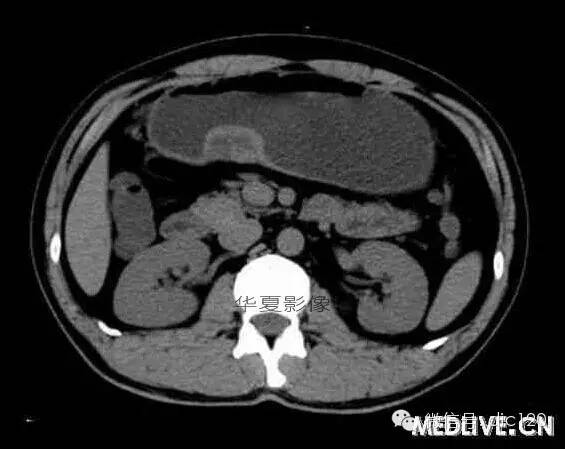

男,36歲,間斷性返酸噯氣3年,3個月前出現上腹疼痛,饑餓時加重。圖1-3為CT平掃,圖4-6分別為CT增強掃描的動脈期、門脈期和延遲期。

CT檢查可見胃幽門前區胃小彎側胃壁局限性增厚、隆起或伴凸向胃腔內的小結節灶,寬基地,境界光整,注射對比劑,增強掃描后,CT值可達50HU以上,與正常胰腺強化相仿。

胃迷走胰腺大多位在距幽門1-6cm的胃竇胃大彎側,粘膜下層內,為1-3cm大小的病灶。 與胃壁以寬基底相,增強掃描病灶表面覆蓋的黏膜明顯強化且連續,病灶內無明顯壞死,病變強化方式類似于正常胰腺組織;當病灶出現邊緣臍凹征或中央導管征時,對EP的診斷具有一定的特異性。